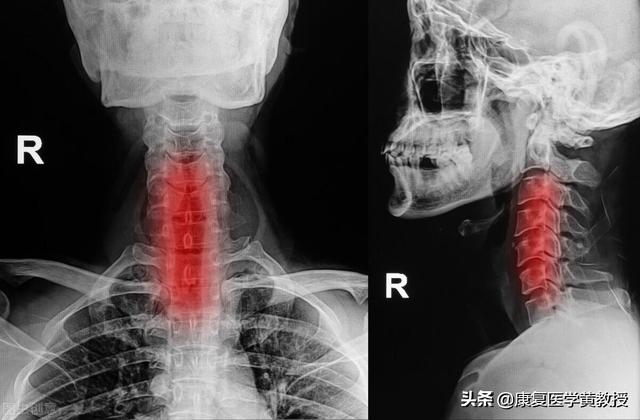

1.まずは病院に行くこと。頸椎症の診断は、X線、CT、MRIなどの従来の画像検査で確認できる。そして症状の重さである;

頸椎が1センチもずれている?伝説の頚椎症だ。 ルイス・クーに同情する。

頚椎症はどのように治療するのですか?

I. トラクション

頚椎牽引は、神経原性頚椎症、頚椎症性頚椎症、交感神経性頚椎症の治療法として選択されることが多いが、脊髄性頚椎症で脊髄の圧迫が顕著なもの、頚椎分節の不安定性が著しいものには禁忌である。